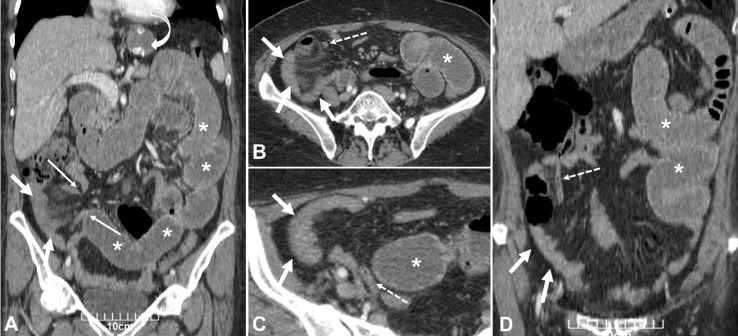

Sleeve gastrectomy is a popular surgical procedure for weight loss. Although it is basically a safe surgery; however, it can lead to serious complications such as intestinal obstruction. The present report describes a 55-year-old woman who attended with complications of abdominal pain and vomiting that underwent laparoscopic exploratory intervention and ileum obstruction due to adherent bands of the appendix was considered as final diagnosis.